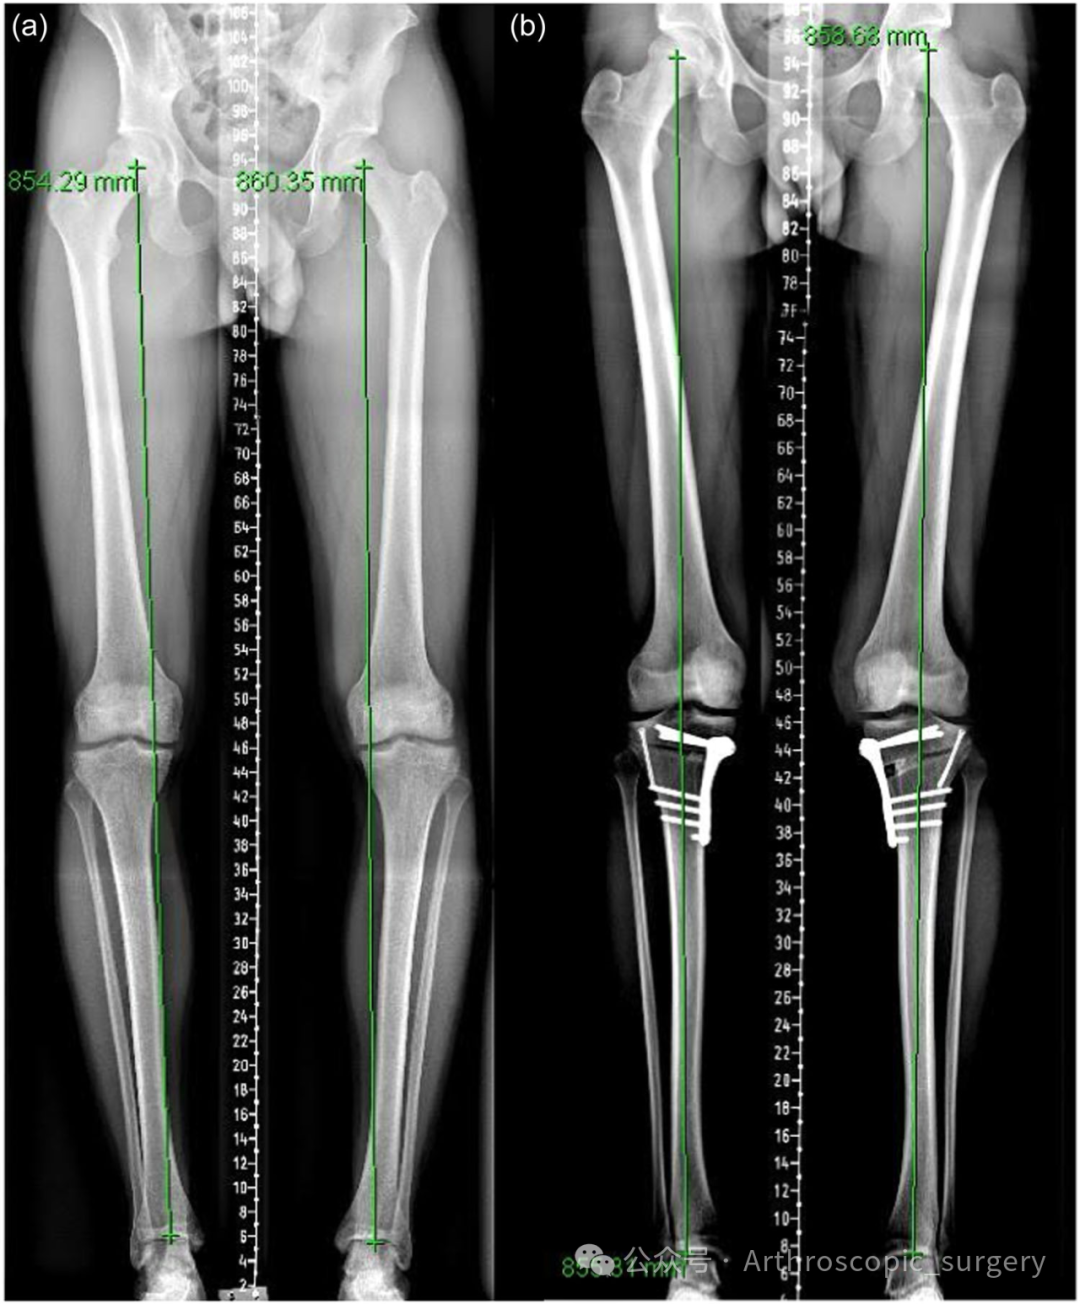

Anteroposterior bilateral long leg standing radiographs (a) preoperative demonstrating bilateral degenerative varus knee with medial mechanical axis deviation. (b) Postoperative bilateral medial opening wedge high tibial osteotomy with neutral mechanical axis.